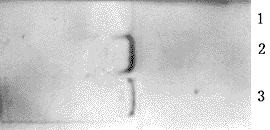

图1显示wt-p53、TDNp53细胞均有p53mRNA的表达(2、3),而pNeo细胞则无p53mRNA的表达(1)。

图1 Northern印迹分析p53的表达

1:pNeo细胞;2:wt-p53细胞;3:TDN p53细胞